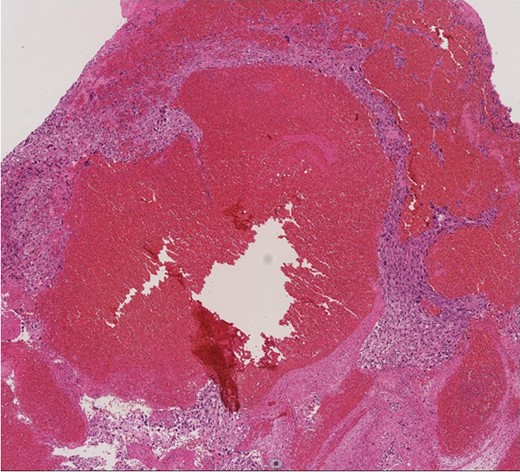

A 60-year-old man presenting with acute onset dyspnea and chest pain was referred to our institution. He had no past medical history. Physical examination was essentially normal except for weak respiratory sounds on the right side. Oxygen saturation was 88%. D-dimer was 1.43 mg/l. The electrocardiogram showed no ST changes. Chest radiography showed an abnormal shadow in the hilum of the right lung. Color Doppler ultrasound showed no deep vein thrombosis. Both the Wells Score and the Revised Geneva Score were 0. Transthoracic echocardiography showed normal left ventricular function (ejection fraction 62%), and no findings of pulmonary hypertension. Contrast-enhanced computed tomography (CT) showed a contrast defect lesion in the right and main pulmonary arteries, as well as a right pleural effusion (Fig. 1). He was initially diagnosed with PE according to the imaging findings and clinical presentation. Anticoagulant therapy (intravenous heparin infusion) was then started. Follow-up CT showed a larger defect lesion in the pulmonary artery, and the decision was then made to proceed with urgent pulmonary embolectomy because it was refractory to anticoagulant therapy. Cardiopulmonary bypass was established with aortic and bicaval cannulation. Deep hypothermic circulatory arrest was used every 10 minutes to obtain a bloodless field during pulmonary embolectomy. The right pulmonary artery was incised, and it was filled with a red, solid mass (Fig. 2). The mass was resected, and the pathological diagnosis during surgery was PAS. Because of the urgent situation, only endarterectomy, not pneumonectomy for radical resection of the tumor, was performed. On postoperative Day 7, CT showed residual lesions in the right pulmonary artery. The pathology report showed high-grade undifferentiated PAS (Fig. 3). The patient refused radical tumor resection by pneumonectomy, as well as postoperative radiation and chemotherapy. He died 5 months after the surgery.

Macro findings of the pulmonary artery show sarcoma and thrombus.